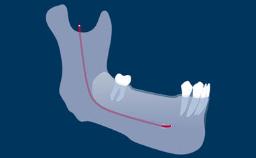

As implant dentistry has evolved, the esthetic outcome of implant therapy has gained increasing importance. As a result both patients and those in the dental profession have become increasingly interested in the attractive esthetic characteristics of all-ceramic prostheses. Extensive research is being devoted to developing, testing, and reviewing the characteristics and performance of ceramic materials in connection with implant therapy. Nevertheless each patient is unique, and it is important to ensure that the appropriate prosthodontic material is selected for each case. This step often requires a team approach in which both the prosthodontic dentist and the dental technician are involved. This module will discuss the different parameters that should influence the decision-making process for selection and use of ceramic materials in implant prostheses.

- describe prosthodontic indications for ceramic materials in implant prostheses and abutments